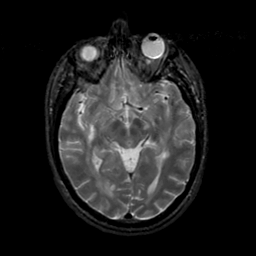

MR Study #19, August 25, 1991 -- Slice #22